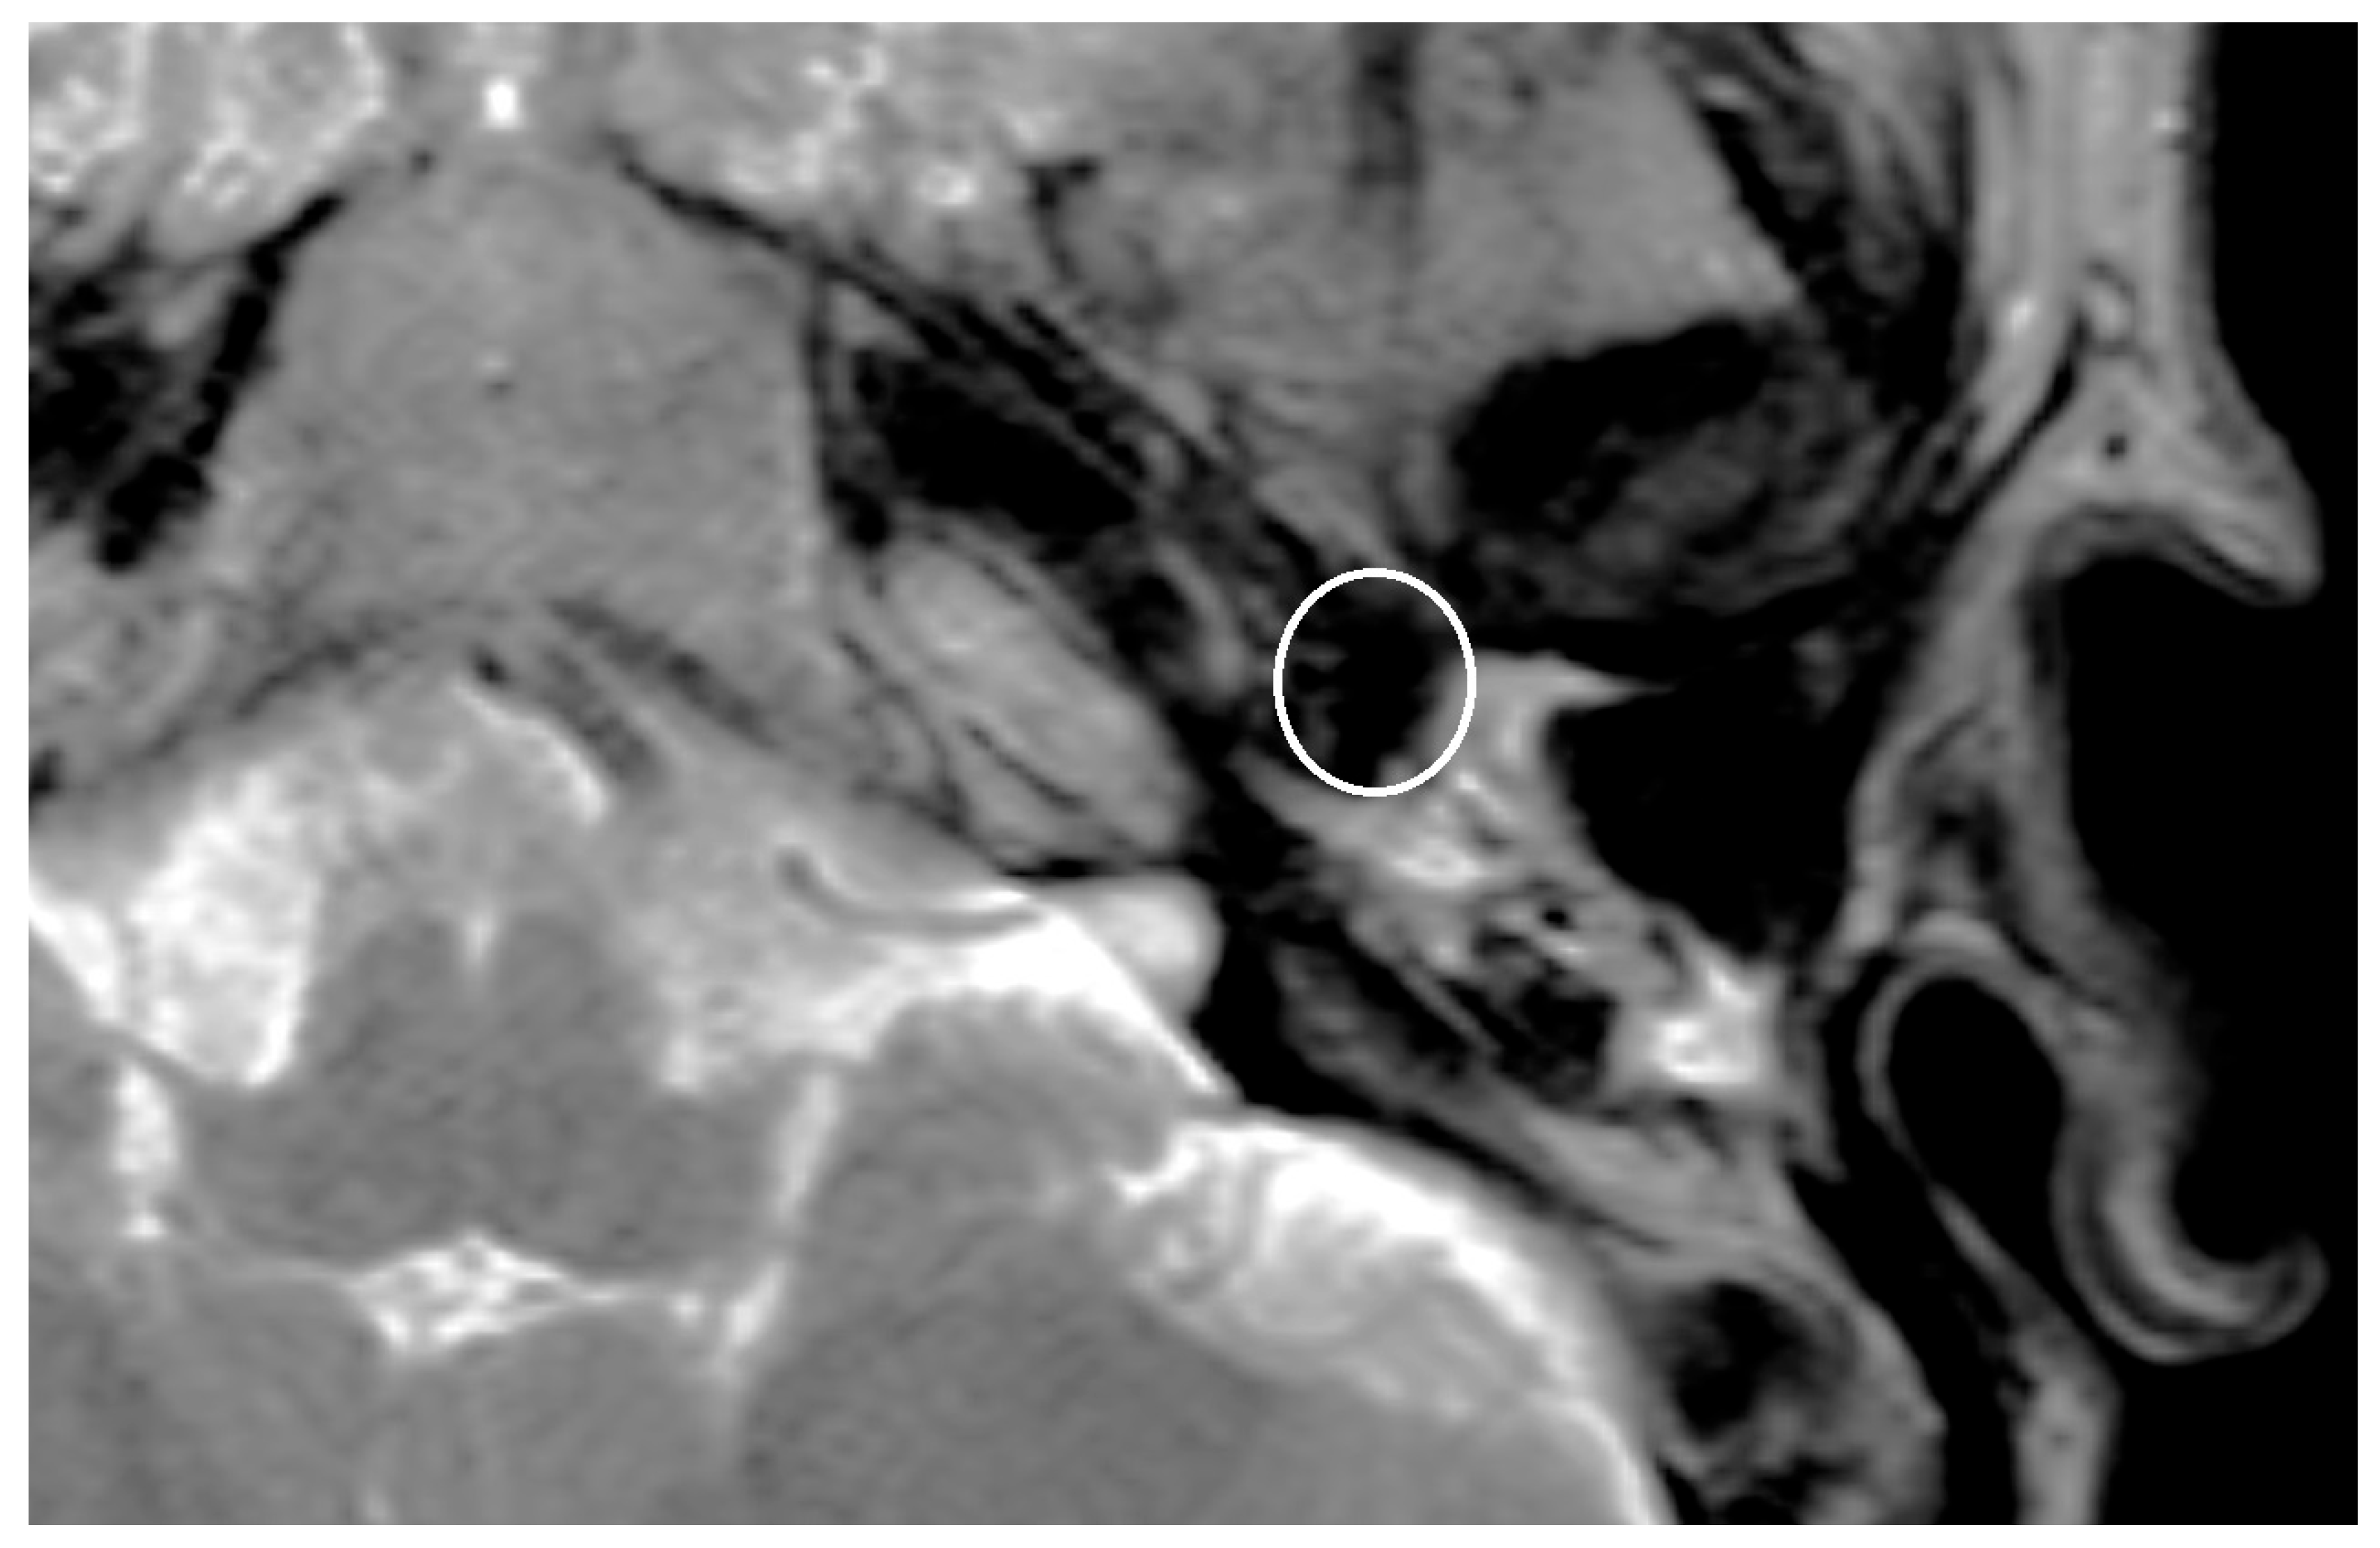

Figure 2. T2-sequence with artifact after implantation of a PORP at the right-sided middle ear, see white ellipsis.

An artifact was detected in all MRI examinations (see Figure 1, Figure 2 and Figure 3).

The artifact measurements firstly done in T1- or T2-sequence showed an average artifact of 3,1 mm for PORP, 4,7 mm for TORP and 3,6 mm for meshes (see Figure 4, Figure 5 and Figure 6). The overall average artifact was 3,8 mm.